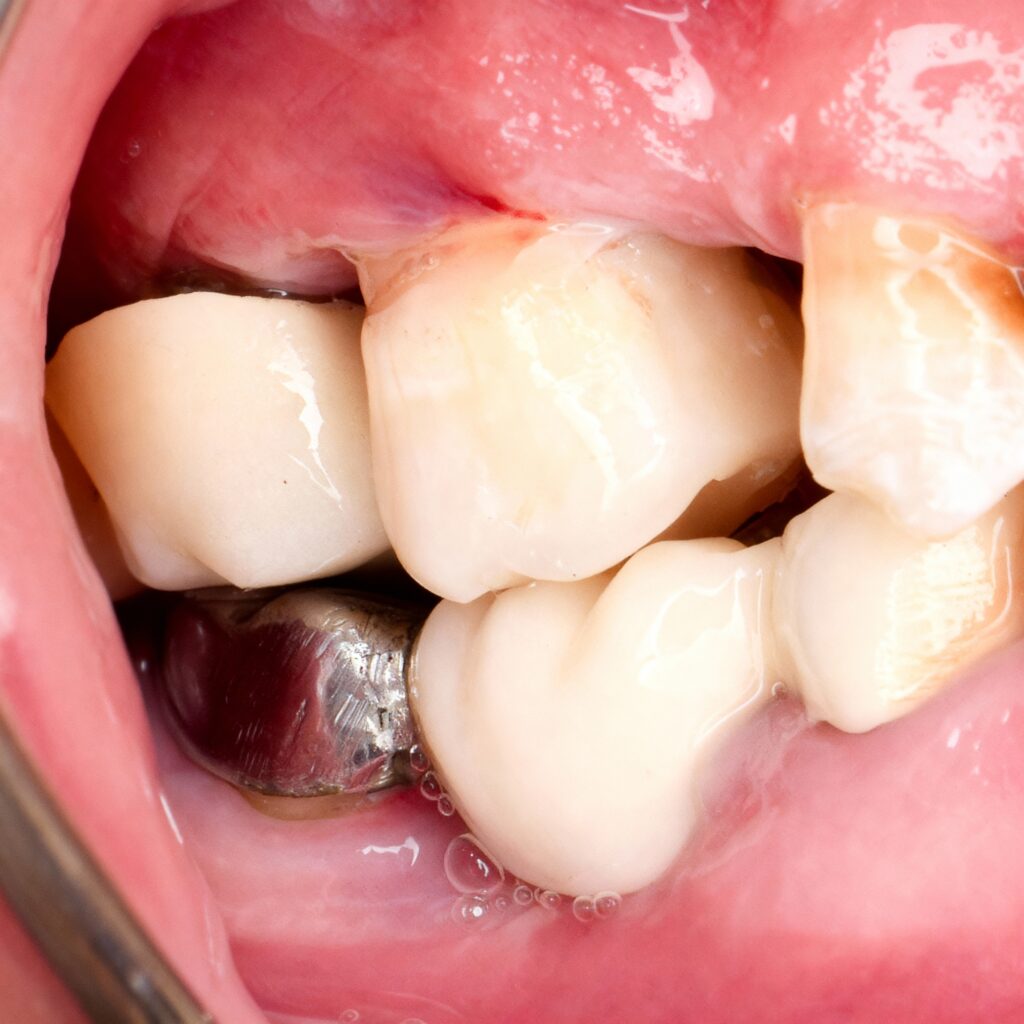

- Endodontically treated posterior tooth

- Moderate to extensive loss of coronal structure